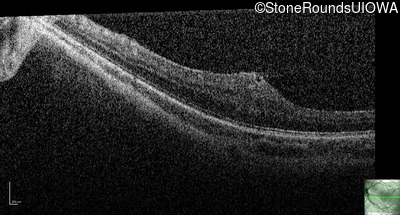

Optical Coherence Tomography - Left - 20/80

Exemplar / OCT Stack